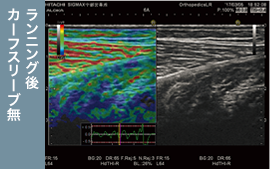

20km走の前後で下腿三頭筋(腓腹筋・ヒラメ筋の内側・外側)の硬度の変化を超音波画像診断装置で測定。カーフスリーブ着用の有無*での比較を行いました。

超音波画像診断装置による検査。

超音波画像診断装置による検査。